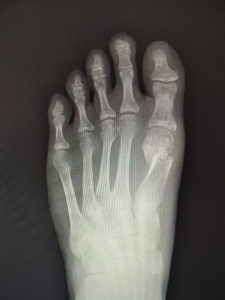

おおむね、外反角が30度以上になると、保存治療はもはやあまり有効ではありません。症状が強く、患者さんと良く吟味の上、希望されれば手術へと進みます。他に根治療法はないが、手術なら根治できます(図5)。ただMP関節の変性性変化があると、痛みや拘縮が残ることがあります。

(図5)

手術前 手術後4年

(図6)

手術前 手術後

(図7)

真田理事長による手術の様子。外反母趾|症例 (左から 手術前、手術後、ワイヤ抜去後)